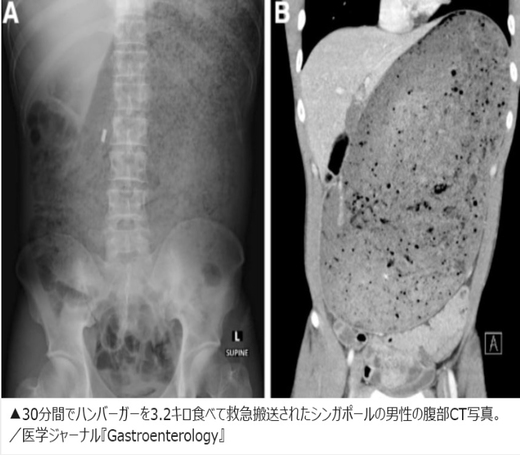

CT撮影の結果、男性の胃と十二指腸は摂取した飲食物で膨らんで巨大になっていた。さらに、消化されていない食べ物が周辺の臓器を圧迫し、すい臓が砕けていた。

公開された男性の腹部CT写真には、へそのすぐ上から肩の近くまで飲食物でパンパンになっている様子がはっきりと写っている。男性は入院し、膨張した胃の圧力を下げるためにカテーテルによる胃の洗浄を受けたが、それでも症状は改善しなかった。